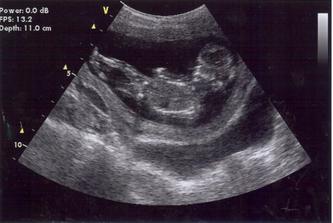

14.10.08 poradna - odebrána krev+moč-výsledky za 14dní, mimísek má 4cm a dostali jsme TĚHOTENSKOU PRŮKAZKU🙂)).............................................27.10.08 poradna - mimísek má 6,5cm, genetický test v naprostém pořádku, riziko se snížilo na 1/9050 - takže téměř žádné-huráááááááá!............................................. 19.11.2008 odběry krve na triplle testy v 16tt - negativní🙂))............................................. 16.12.2008 poradna - vše v pořádku.............................................18.12.2008 velký ultrazvuk - mimísek je v naprostým pořádku, srdčko i všechno ostatní funguje jek má🙂)))............................................. 13.1.2009 poradna + test na cukr............................................. 27.1.2009 poradna - cokrovka je negativní, můžeme mlsat dál🙂............................................. 13.2.2009 4D ultrazvuk-mimísek se nám pořád skovával za ručičky, ale nakonec jsme ho přemluvili a aspoň na chvilku se nám ukázal🙂)............................................. 17.2.2009 poradna- prcek už je hlavičkou dolů a připravenej jít ven, navíc mi strašně tvrdne břicho takže mi dr. zvýšil dávku magnézia a musíme ležet............................................. 2.3.2009 velký ultrazvuk v 31tt - prcek je v pořádku a už má 1700g ............................................. 17.3.2009 poradna - vše ok, prcek má 2100g ............................................. 18.3.2009 sepsání porodopisu ............................................. 26.3.2009 nástup na mateřskou🙂